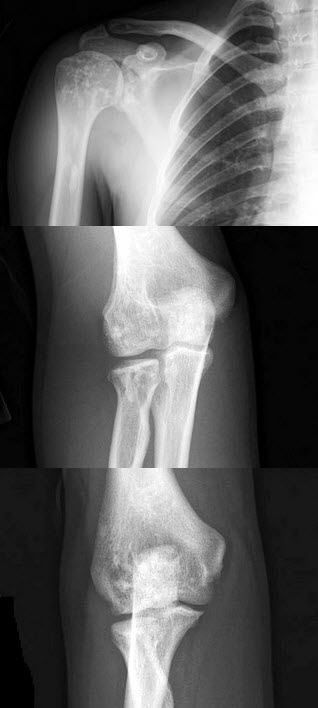

38、单项选择题

女,71岁,左肩痛,系统性红斑狼疮服用高剂量的类固醇半年,结合图像,最可能的诊断是()

A.化脓性关节炎

B.类风湿关节炎

C.骨纤维肉瘤

D.肱骨头缺血坏死

E.肩关节结核

点击查看答案

42、单项选择题

男,6岁,髋部疼痛、跛行半年,结合图像,最可能的诊断是()

A.髋关节结核

B.股骨头骨骺缺血坏死

C.骨肉瘤

D.骨囊肿

E.软骨肉瘤